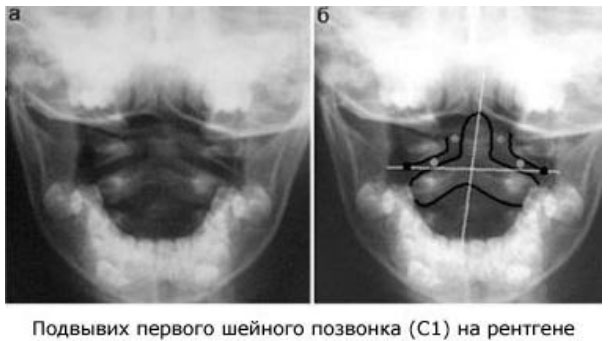

| Диагностика | Клинический осмотр (пальпация, оценка объема движений), рентгенография шейного отдела позвоночника (в различных проекциях, функциональные снимки), КТ, МРТ. | Позволяет точно определить степень и характер смещения. |

Диагностика основывается на наличии специфических жалоб, связанных с подвывихами определенного сустава, а также на характере нарушений его функциональности. Важную роль играют результаты инструментальных исследований, таких как рентгенография в различных проекциях, компьютерная томография (КТ) и магнитно-резонансная томография (МРТ).